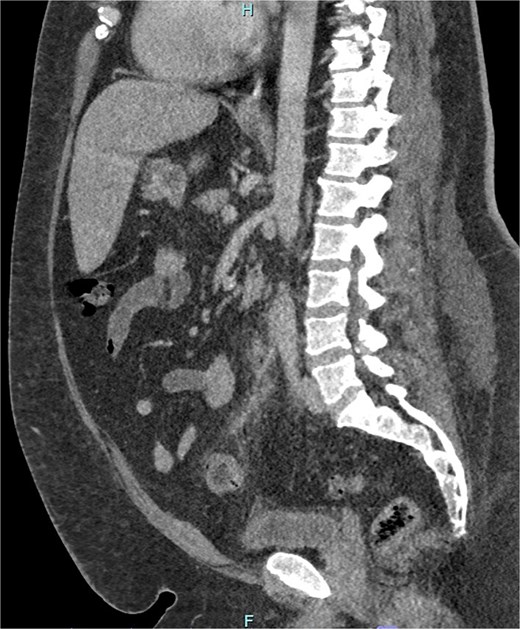

He received intravenous cannulation and initial fluid resuscitation. His blood demonstrated leucocytosis (11.59), C-reactive protein of 213, and a normal coagulation profile. The lactate measured 1.3. CT imaging with portal venous contrast demonstrated sigmoid diverticulitis, complicated by inferior mesenteric vein thrombosis. Features of mesenteric fat stranding were seen surrounding the IMV and left colic branch, with reduced opacification of the vessels in this area (Figs 1 and 2). There was no discrete collection identified. The patient returned a positive blood culture, with growth of Bacteroides fragilis present from the day of admission.

Sagittal CT image demonstrating portal venous contrast phase abdomen, with inflammatory fat stranding and wall enhancement of the IMV and branches.